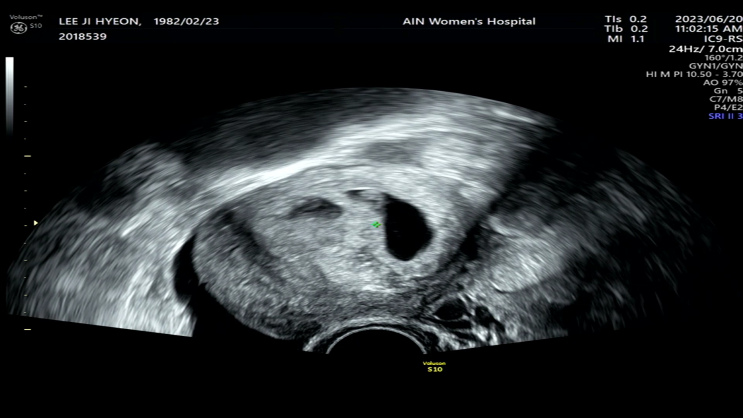

[임신일기]9주 4일차 / 젤리곰 확인하는 날, 니프티 검사 종류와 가격

그동안 1주일만에 갔던 병원을 2주만에 방문하는 날이다. 아이들이 잘 자라고 있어 굳이 1주일만에 올 필요...